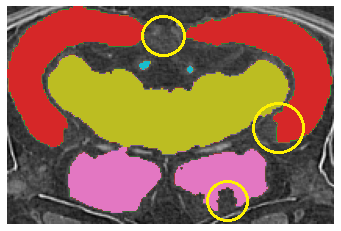

Fig.ย 2: Examples of (a) Input image, (b) ground truth, and segmentation results by (c) the Teacher (Fully Supervised), (d) the Student model by the proposed method.

First, we present a quantitative comparison of the results of the proposed method with the Fully Supervised model as a baseline in Tableย 1. The proposed method clearly outperforms the baseline in both the low and full data regimes. These results demonstrate that our method consistently outperformed the baseline. In addition, the proposed method using only seven labeled volumes provided better performance than the baseline using all available training data volumes, confirming the proposed method can improve the Medaka segmentation performance. Remarkably, our method using only two volumes of the labeled data achieved better results than the Fully Supervised method with 12 labeled volumes. Second, we visually compare the results of the segmentation as shown in Fig.ย 2. We marked the problematic areas of the sample with yellow circles in Fig.ย 2 (c). While the prediction of the proposed method clearly has its own peculiarities of segmentation, the provided result is smoother spatially and closer to the ground truth.